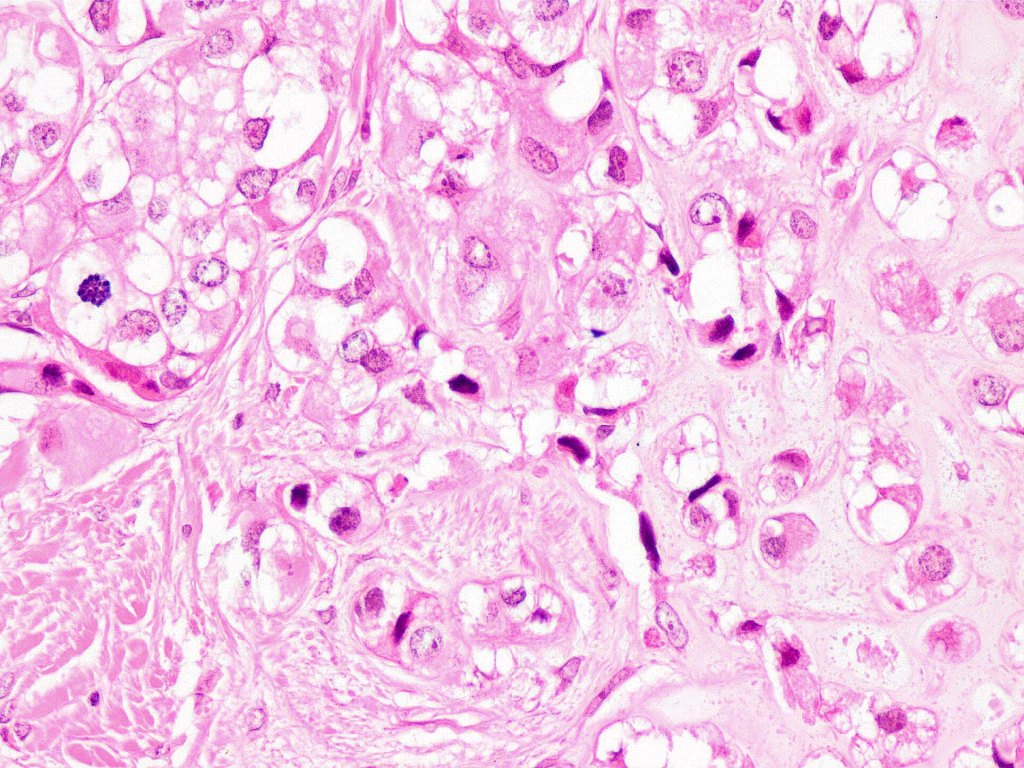

•Admixture of squamous carcinoma & pleomorphic spindled cell, osteoid, chondroid, MFH-like +/- osteoclast-like giant cells & rarely, smooth muscle, skeletal muscle, myofibroblastic or angiosarcomatous elements

•Epithelial component AE1/AE3, CK5/6 & p63 +ve;

•Mesenchymal element variable CD10, CD68, CD99 & lineage specific markers +ve; scattered cells may show weak keratin expression